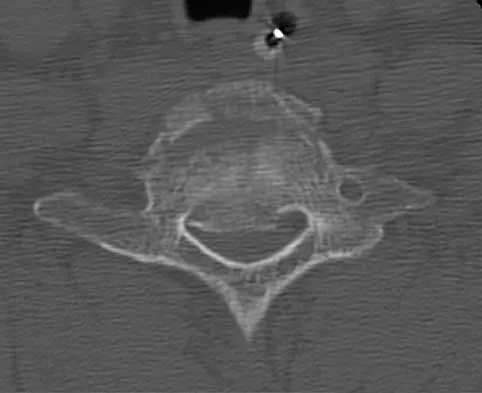

Question 17

Figure 11a shows the AP pelvis radiograph of a 25-year-old man who sustained a spinal cord injury 10 years ago. A bone scan and a CT scan are shown in Figures 11b and 11c. To prevent recurrence after resection, management should consist of

Explanation